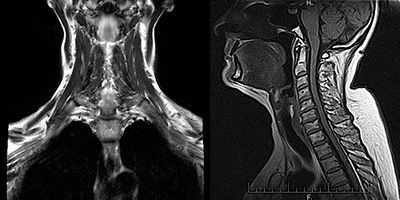

Сложность диагностики состоит в том, что у пациентов с миастенией в начале заболевания может не быть каких-либо четких жалоб и симптоматики. При нейровизуализации (КТ или МРТ) нет значимых отклонений в структурах центральной нервной системы. Только у 30% заболевших тимус увеличивается, либо в нем выявляются новообразования. Мышцы при осмотре так же никак не изменены, патология может выявляться только при микроскопическом исследовании.

Компьютерная томография средостения. Используется для исключения тимомы - опухоли вилочковой железы, которая может продуцировать антитела.

Ценную информацию может дать компьютерная томография органов средостения. В силу того, что большой процент случаев миастении можно связать с объемными процессами в вилочковой железе, КТ средостения таким больным проводят достаточно часто.